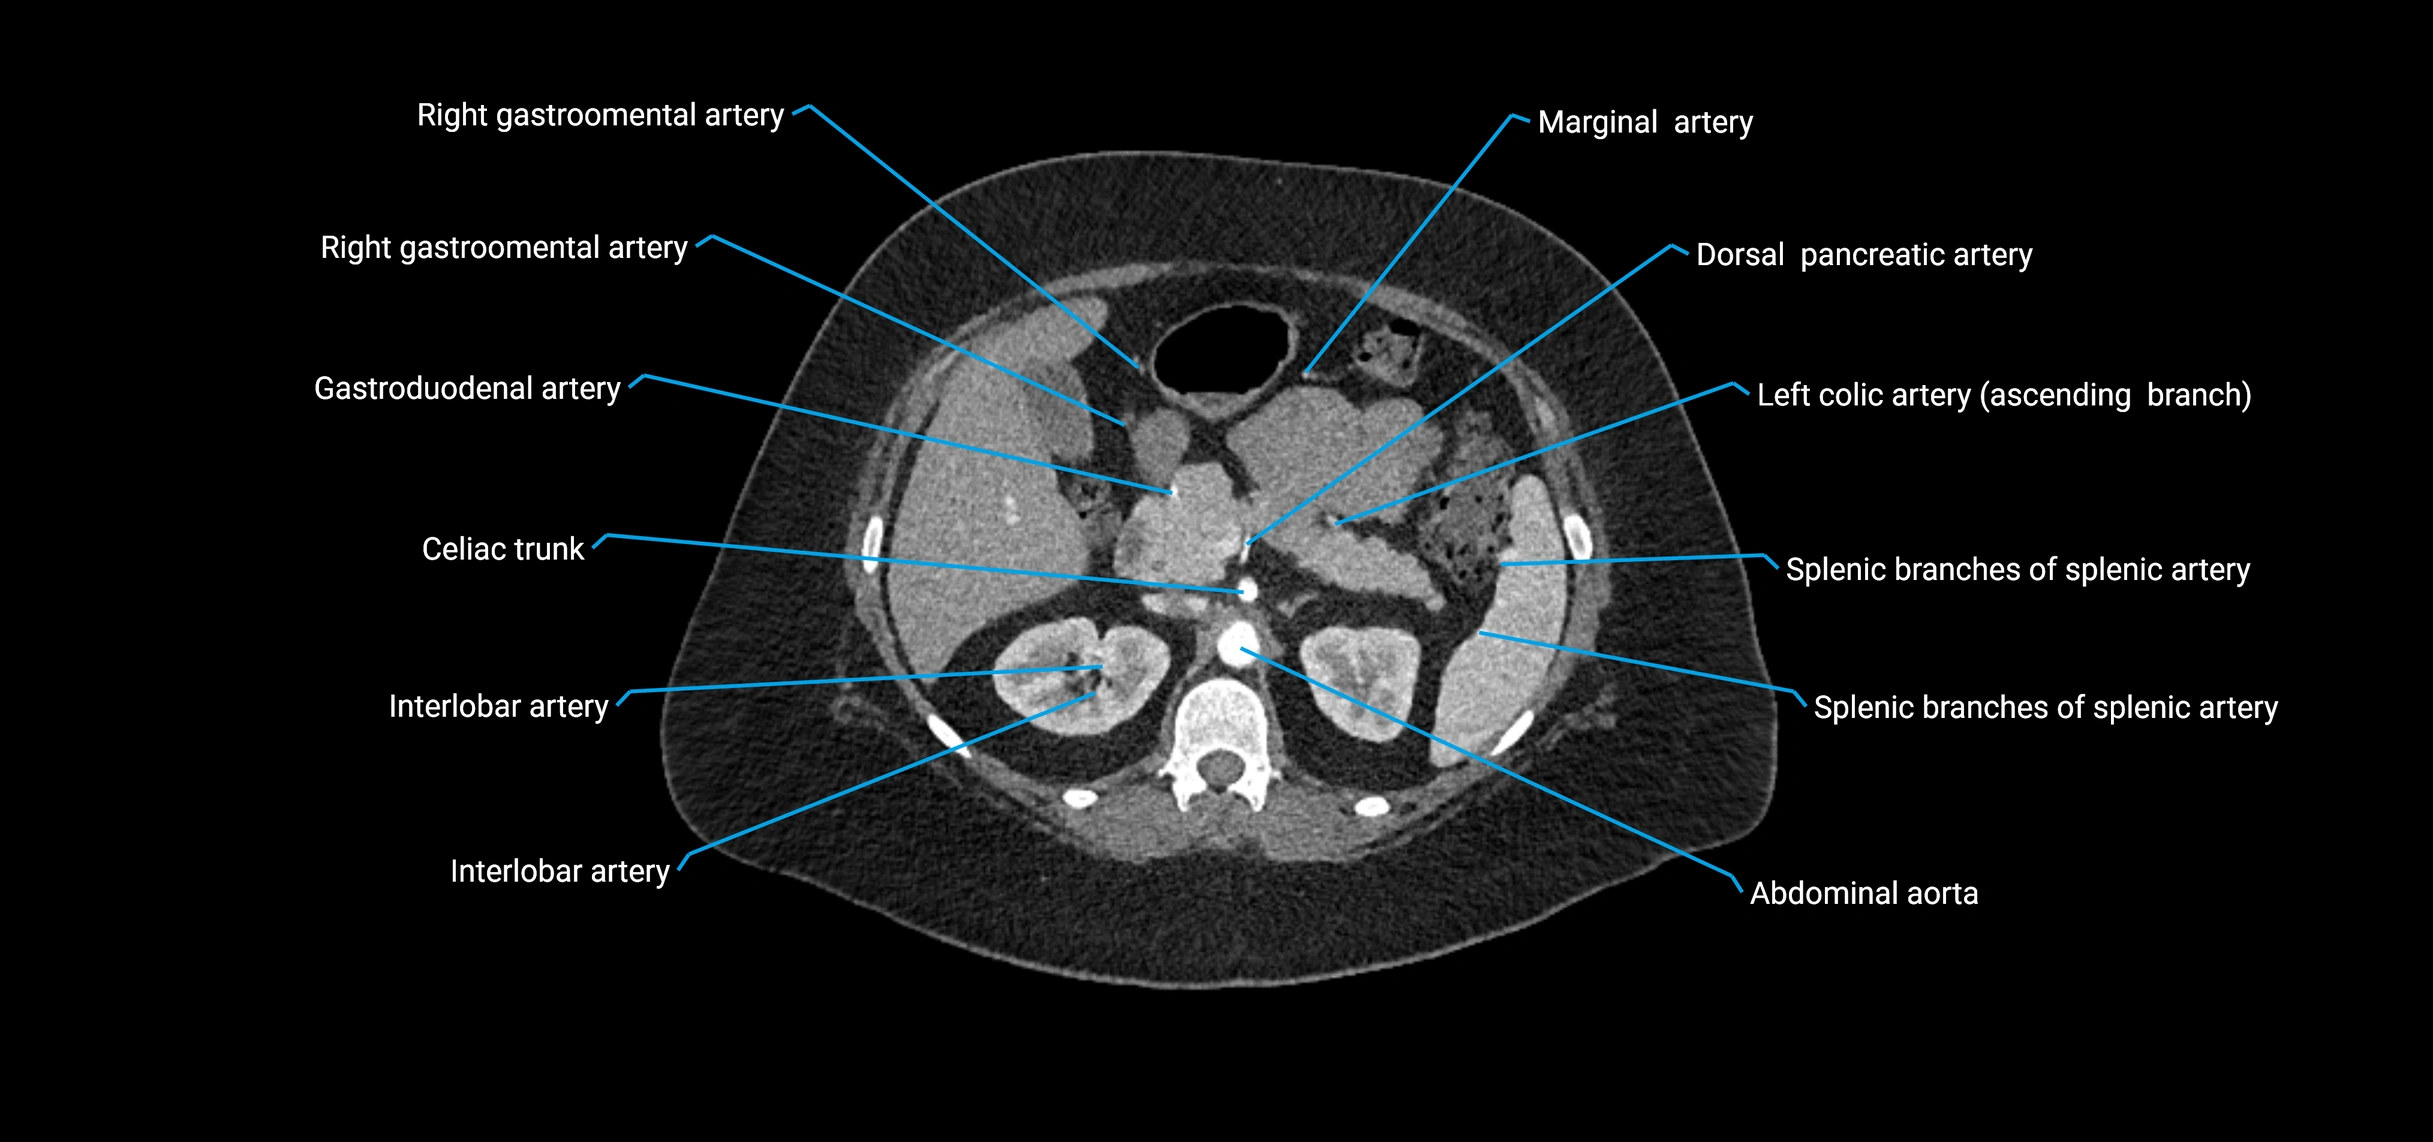

CT Appearance

Non-contrast CT:

• Appears as a tubular soft tissue structure anterior to vertebral bodies

• Calcified atherosclerotic plaques appear as hyperdense foci along the wall

• Useful for screening abdominal aortic aneurysm (AAA) size and mural calcification

Contrast-enhanced CT (CTA):

• Gold standard for abdominal aortic imaging

• Provides excellent detail of lumen, wall, aneurysm, thrombus, and branch vessels

• Multiplanar and 3D reconstructions help in aneurysm measurement, stent graft planning, and dissection evaluation

• Detects acute rupture, traumatic injury, or occlusion with high sensitivity